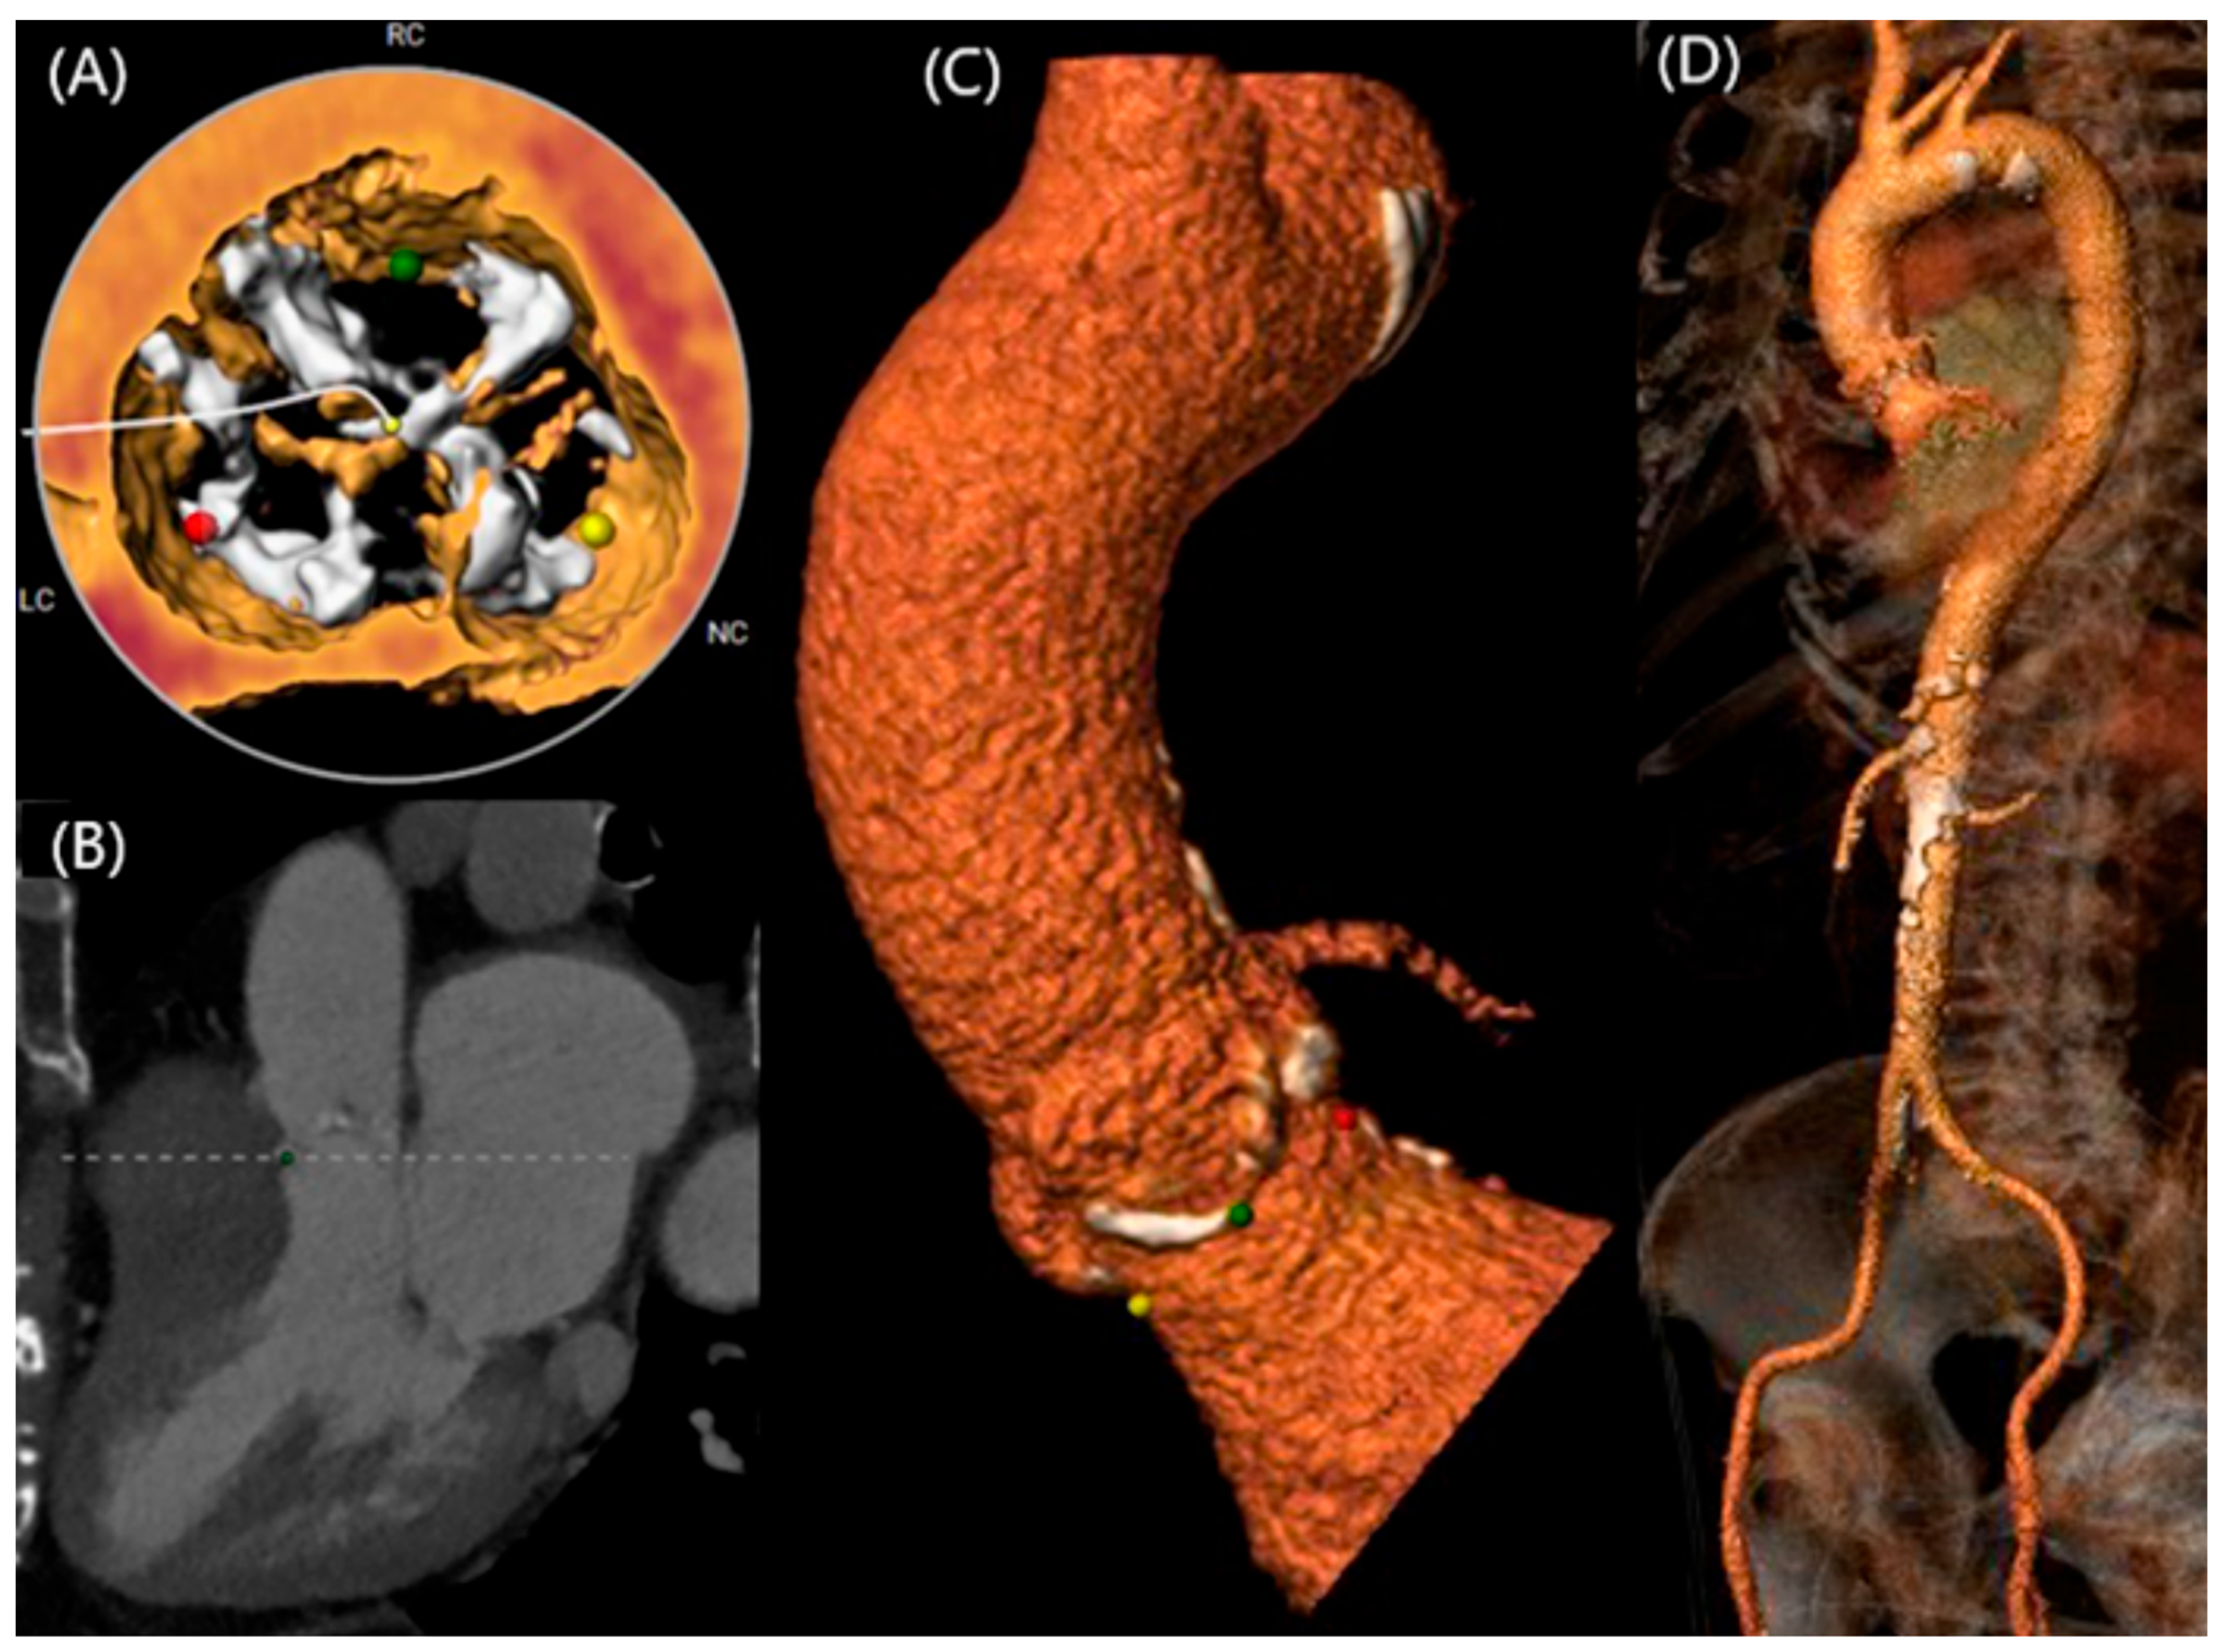

- Kawamori, H.; Yoon, S.H.; Chakravarty, T.; Maeno, Y.; Kashif, M.; Israr, S.; Abramowitz, Y.; Mangat, G.; Miyasaka, M.; Rami, T.; et al. Computed tomography characteristics of the aortic valve and the geometry of SAPIEN 3 transcatheter heart valve in patients with bicuspid aortic valve disease. Eur. Heart J. Cardiovasc. Imaging 2018, 19, 1408–1418. [Google Scholar] [CrossRef]